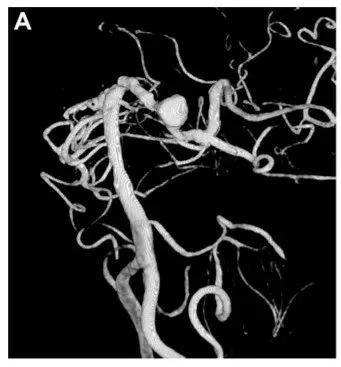

影像学检查显示右侧颈内动脉重度狭窄,同时左侧大脑后动脉(PCA)P1-P2交界处存在一大小为10×12 mm的梭形动脉瘤。

术前 3D-DSA 显示位于左侧 P1-P2 交界处动脉瘤。

A,术前 3D-DSA 显示位于左侧 P1-P2 交界处动脉瘤。B,术后3D-CTA显示左侧 PCA 区血管穿支(箭头)和重建的 PTA 血管(箭头)血流通畅。